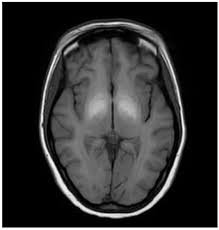

The truth is, an MRI can reveal critical details about your health that no other scan can match. Unlike X-rays or CT scans, which mainly show bones and dense structures, an MRI captures high-resolution images of soft tissues, including the brain, nerves, muscles, organs, joints, and blood vessels.

- ✔ Brain changes linked to dizziness, seizures, headaches, and memory issues